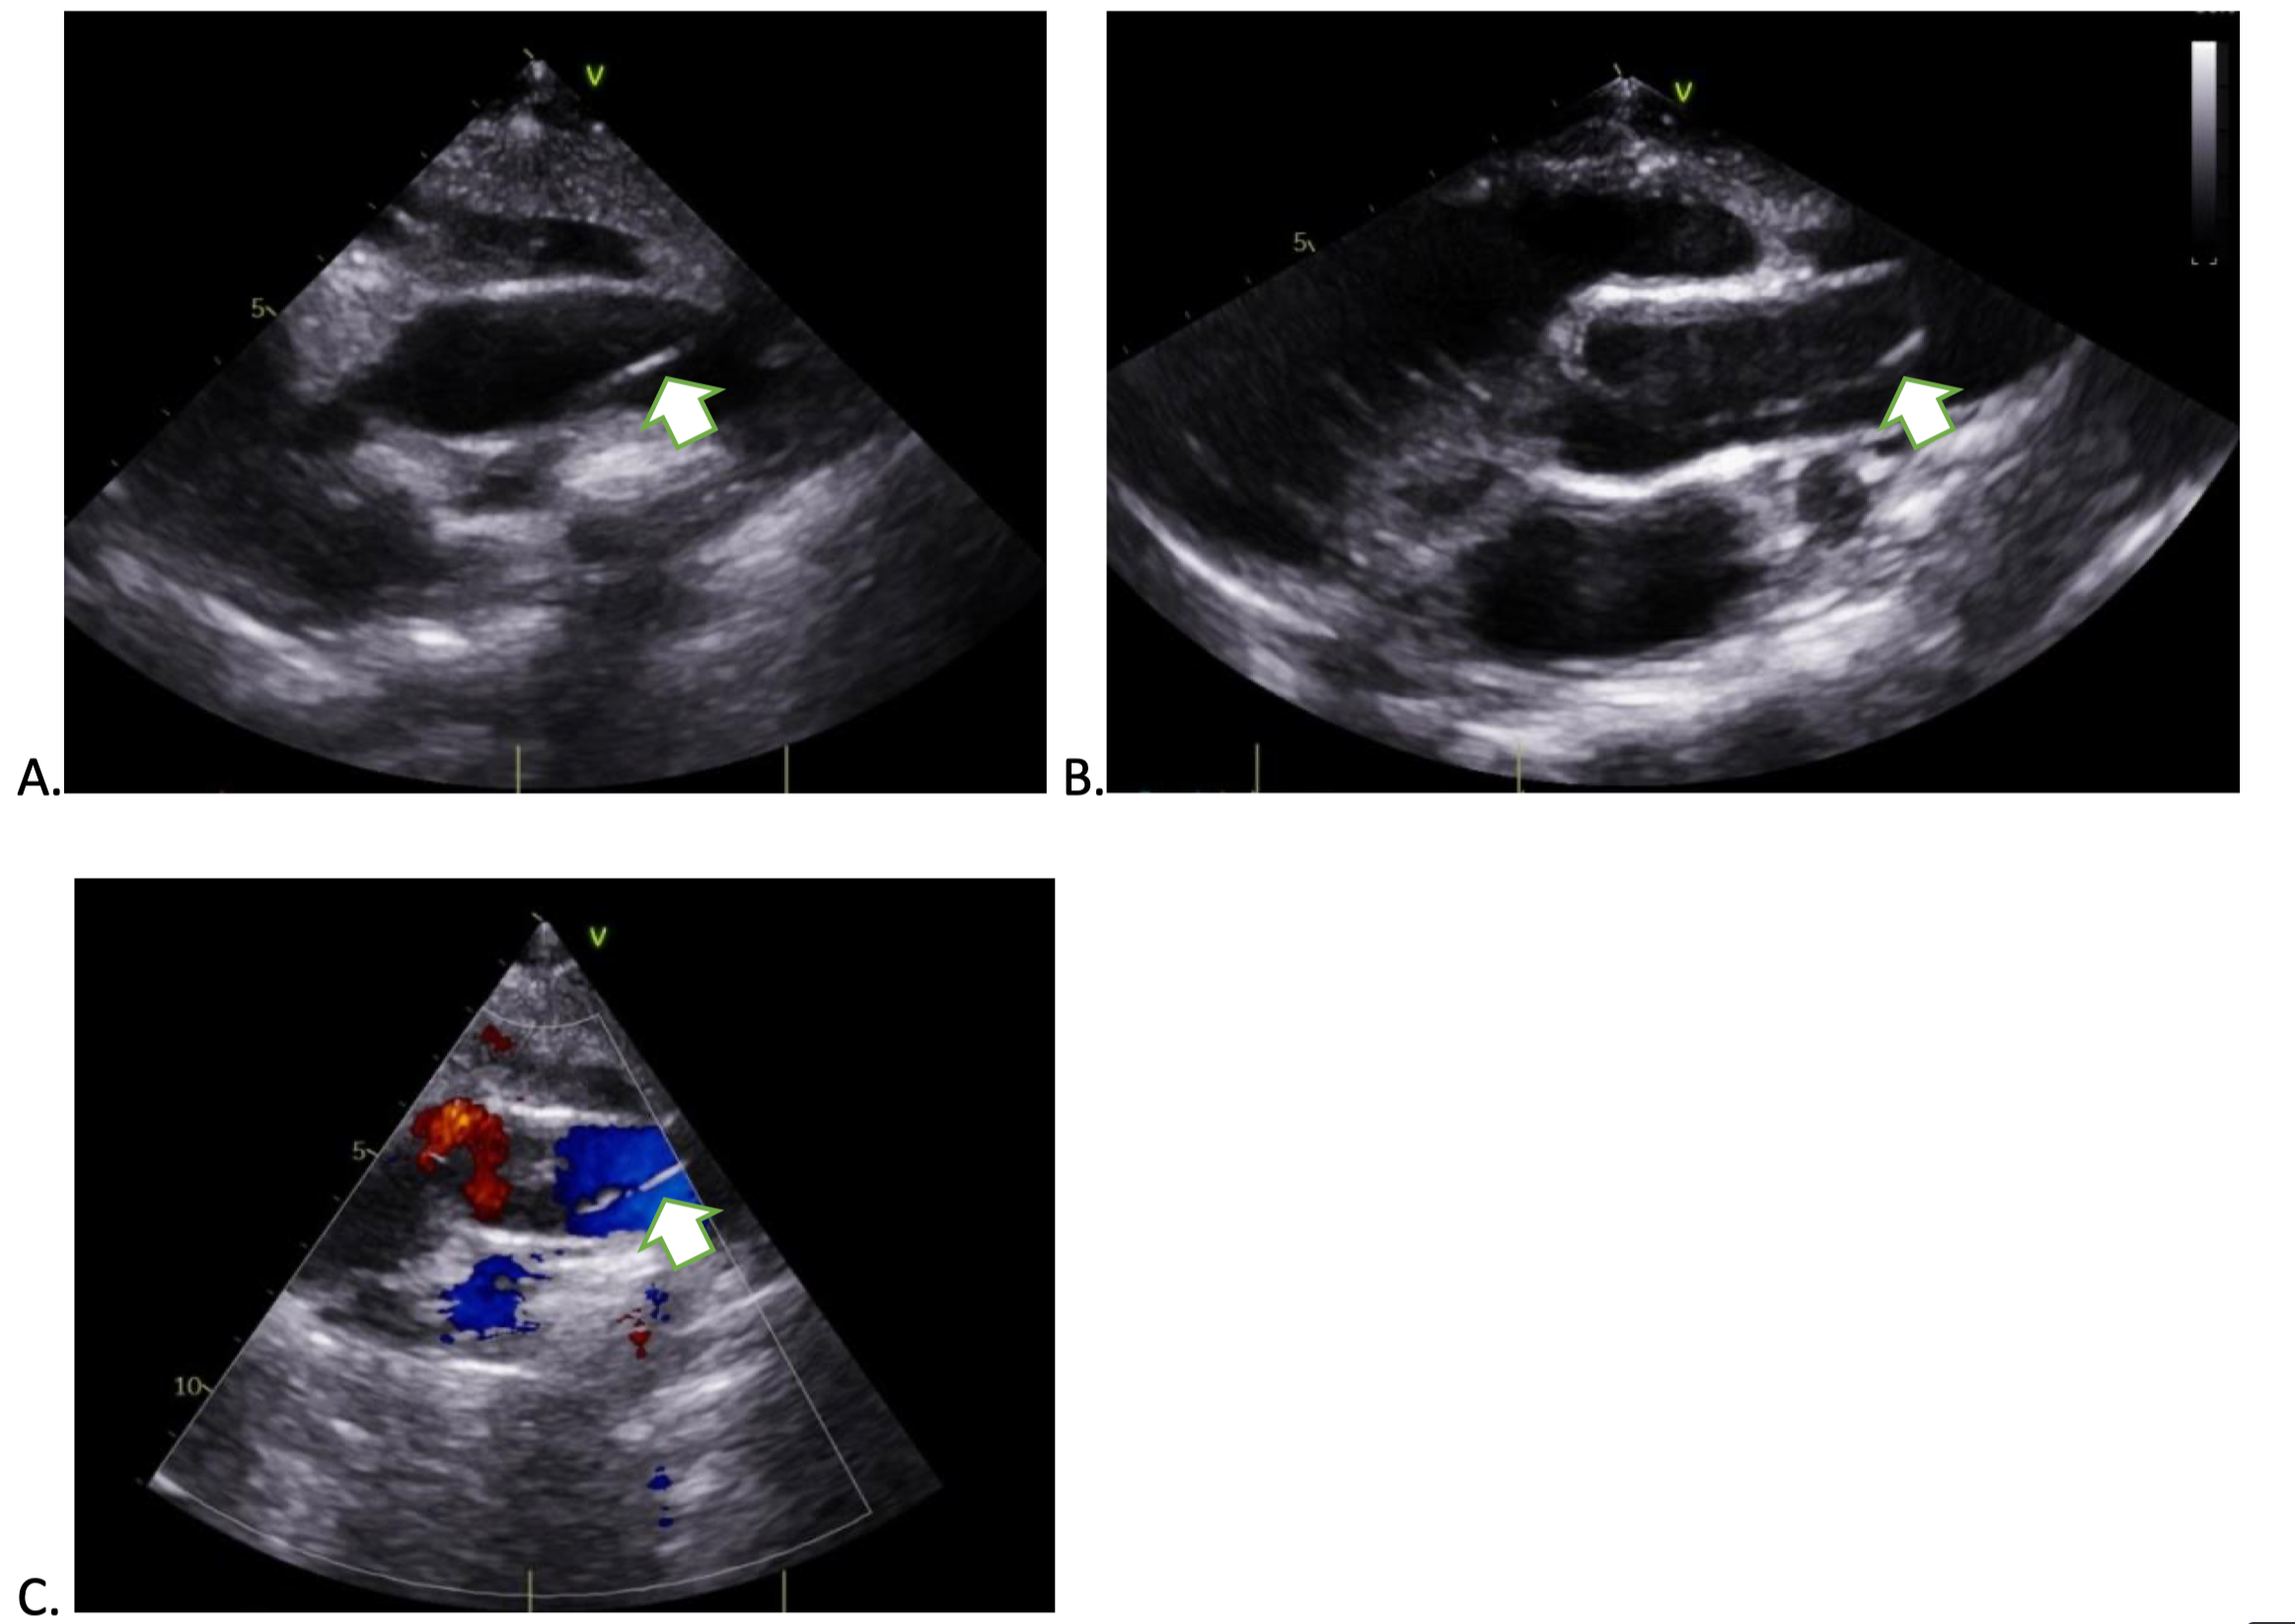

A 12-year-old male with a remote history of self-resolving dyspnea and previously noted trivial mitral regurgitation presented for routine follow-up. He was clinically well with no cardiac symptoms, normal vital signs, and an unremarkable physical exam. Echocardiography revealed an apparent intimal flap (Figure 1-3) in the proximal ascending aorta, raising concern for aortic dissection. There was no associated turbulent flow, pericardial effusion, or signs of hemodynamic compromise. Due to the gravity of potential dissection, a contrast-enhanced computed tomography (CT) aortogram was performed.

CT imaging showed normal aortic anatomy with no evidence of dissection, intimal flap, aneurysm, or other structural abnormalities. Retrospective echocardiographic image review suggested the finding was likely an artifact, possibly due to reverberation or suboptimal transducer angulation. A repeat echocardiogram three months later showed a persistent but less prominent artifact. No intervention was required, and the patient remained asymptomatic.